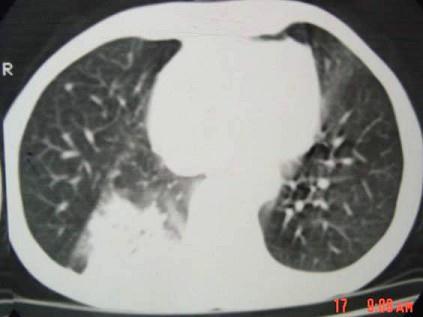

问题 男,40岁,胸背疼痛一周,消瘦一月,CT检查如图,最可能的诊断为 ( )

选项 A、右下肺肺泡癌 B、右下肺炎性假瘤 C、右下肺脓肿 D、右下肺炎 E、右下肺结核

答案 A